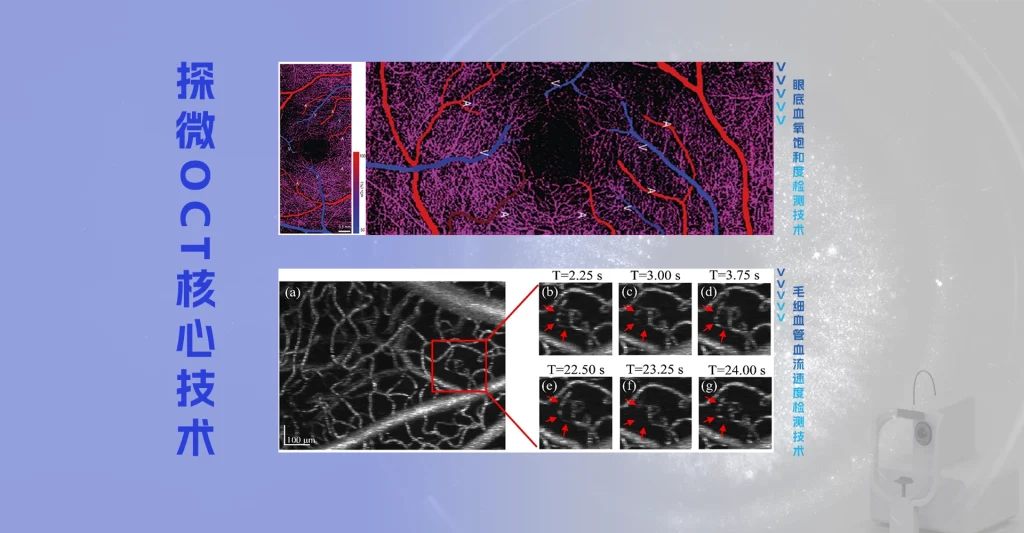

- OCTA广域血管造影成像

- 血管网量化分析

• 24mm×20mm 眼底血流 OCTA

• 血流 OCTA 超过 100亿数据点

• 血流与结构全面量化参数